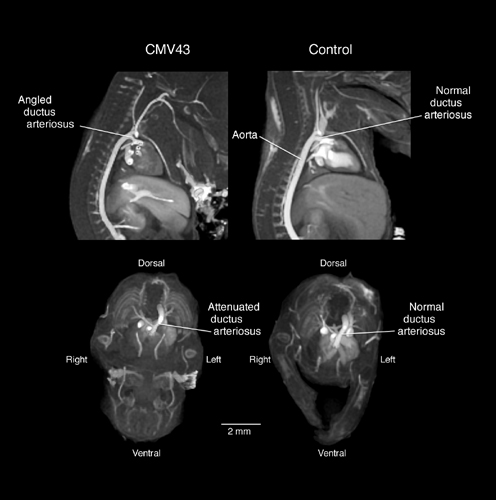

Magnetic resonance images showing disruption of normal development in the mouse embryo with over-expression of CMV43, a connexin gene. (Animal model courtesy of Cecilia Lo).